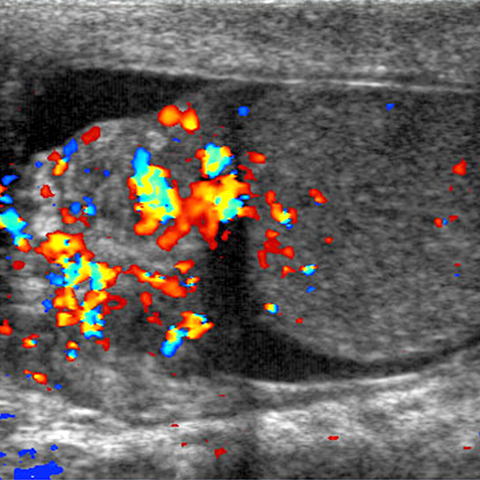

26-year-old-male presents with scrotal swelling and pain. [1 of 2]